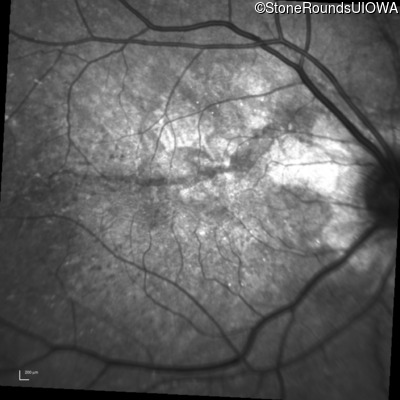

Optical Coherence Tomography - Left - 20/20 -1

Exemplar / OCT Stack

Infrared Fundus Photograph - Left - 20/20 -1

Exemplar